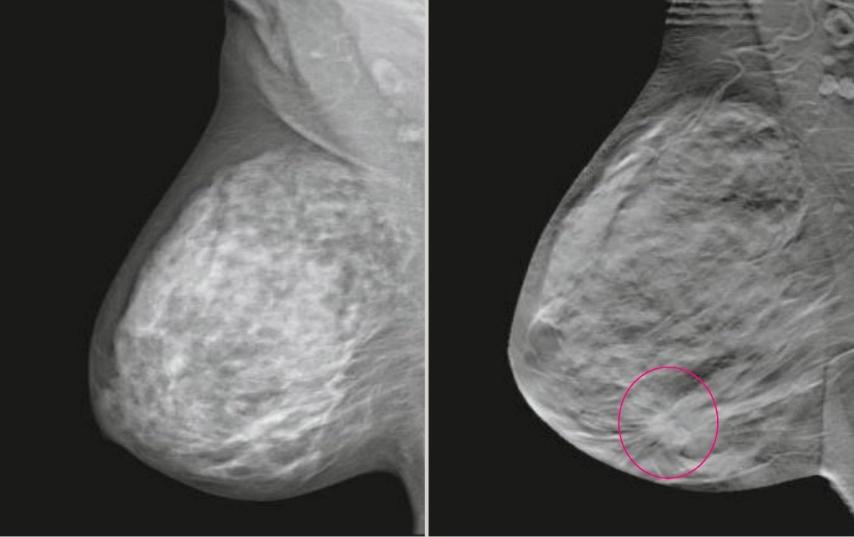

Метод прицельной маммографии с увеличением применяется для более детального исследования определенной области молочной железы. Он отличается высокой точностью диагностики. В отличие от обычной маммографии, которая предоставляет более общую информацию о состоянии молочных желез, прицельная маммография с увеличением позволяет получить точные данные о процессах, происходящих в тканях, благодаря методу компрессии конкретного участка.